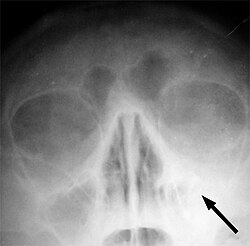

Stupanj promjena kod aerosinusitisa prema simptomatologiji dijeli se u tri razine;. [9] ,[10]

- prvi stupanj karakteriziraju blage prolazne tegobe bez vidljivih promjena na rendgenu,

- drugi stupanj karakteriziraju teški bolovi u narednih 24.sata, sa zadebljanjem sluznice sinusa koje se vidi na rendgenu,

- treći stupanj karakteriziraju jaki bolovi u trajanju više od 24. sata, a na rendgenu se konstatiraju ozbiljne promjene, pojava sekreta i zadebljanja sluzokože sinusa. Naknadno se može javiti krvarenje iz nosa i akutna upala sinusa.